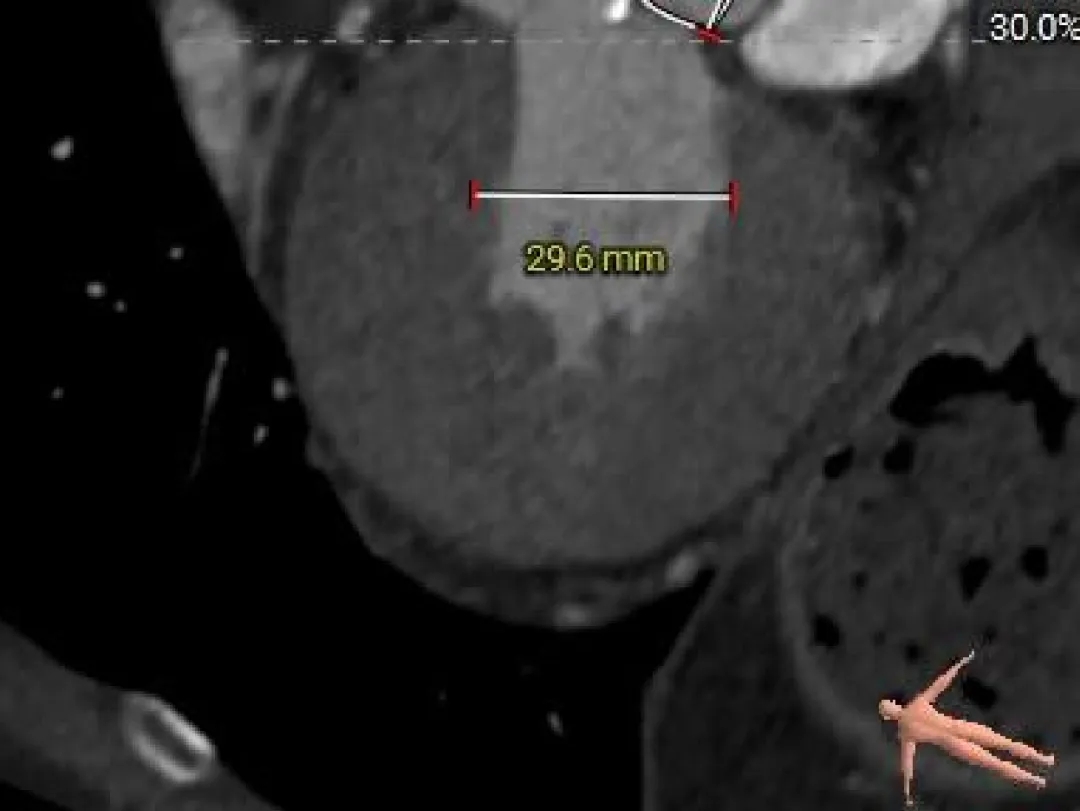

主动脉根部测量

Annulus

21.9mm

LVOT

22.3mm

钙化积分

715mm3

STJ

34.9mm

AAO

42.2mm

SOV

30.4mm*37mm

-

Type-0二叶瓣,中-重度钙化

瓣环径约21.9mm,敞口型流出道

升主增宽

瓣上结构测量

Super-Annulus 2mm 23.2mm

Super-Annulus 4mm 23.4mm

Super-Annulus 6mm 24.2mm

Super-Annulus 8mm 24.7mm

68°横位心

瓣膜选择:ScienCrown TAVTF25mm 0位定位释放;